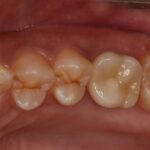

治療後

術後4ヵ月で最終的なセラミック冠を装着しています。

機能的にも見た目も満足いただける仕上がりになりました。